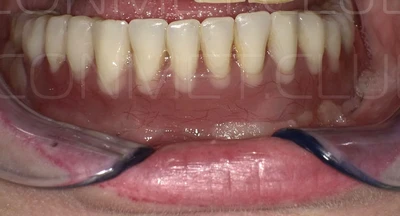

Новые, искусственные зубы фиксируются к этому имплантату стандартными, трансокклюзионными винтами на 1-14 день (в данном клиническом случае на 5 сутки) и по существу являются несъемными!

И в-четвертых: небольшой фрагмент из операции по восстановлению всех утраченных зубов на верхней челюсти. По сути эта операция полностью повторяет протокол и этапность операции представленной в первой части статьи, за исключением того, что искусственные зубы были зафиксированы сразу после операции. Со слов самой пациентки, процесс жевания был совершенно безболезненным с самого первого дня.

Результаты проведенных в 2017-2018 году операций субпериостальной имплантации показали их высокую эффективность, очень быструю адаптацию пациентов к новым зубам и отсутствие послеоперационного болевого синдрома. Интересной особенностью является труднодиагносцируемая, но точно присутствующая микроподвижность имплантатов спустя 6-12 месяцев. Учитывая данную особенность надо категорически избегать объединения субпериостальных имплантатов с естественными зубами или внутрикостными имплантатами!